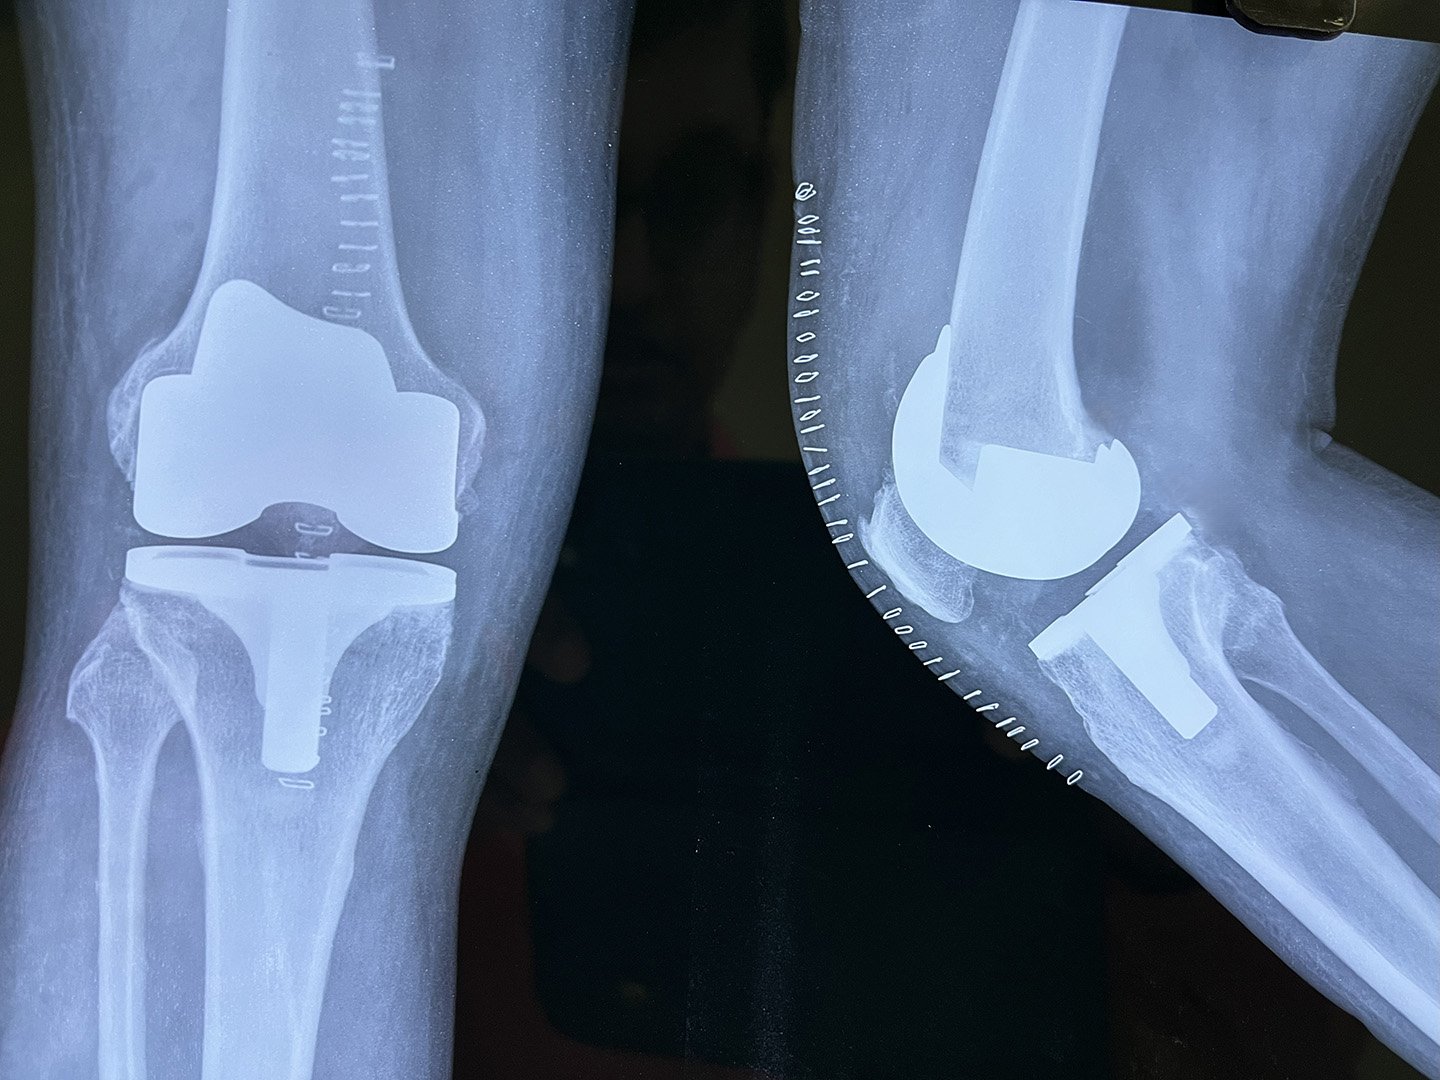

Post-Op X-Ray

Implant Oxinium

OA Knee with Fixed Flexion Deformity & Non correctable Varus